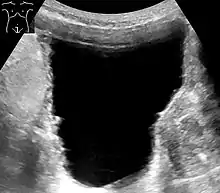

- صورة صوتية: يتم استخدام الصورة الصوتية لرؤية الكلى والمثانة، تحديد قدرة المثانة على تخزين البول، وتحديد كمية البول المتبقية بعد التبول. يساعد هذا بمعرفة إذا ما كان هناك مشكلة في إفراغ المثانة.